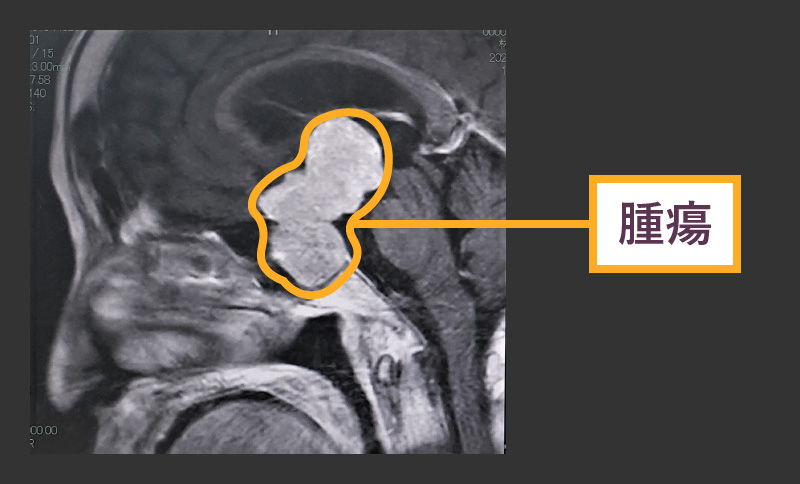

下垂体は脳の基部にあります。体中のさまざまな器官に作用するホルモンを分泌します。下垂体腫瘍には癌性と非癌性(良性)があります。どちらのタイプでも症状を引き起こしている場合は手術が必要になる場合があります。

腫瘍が次のような場合には、手術が必要になることがあります。

- 脳内の構造を圧縮する

- ホルモンの分泌

- 急速に成長している